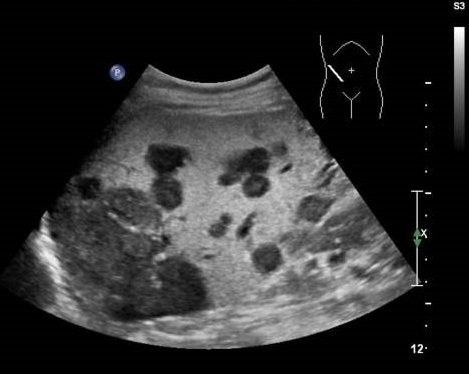

Image echographique du metastase hepatique :

Aspect est variable , souvent multiple a des nodules hypo ,

isoechogene avec contour de hypoechogene , parfoie est

hyperechogene

Aspect hypoechogen des

metastases cancereuse du foie |

Aspect de reverse

hyperchogene des metastases du foie |